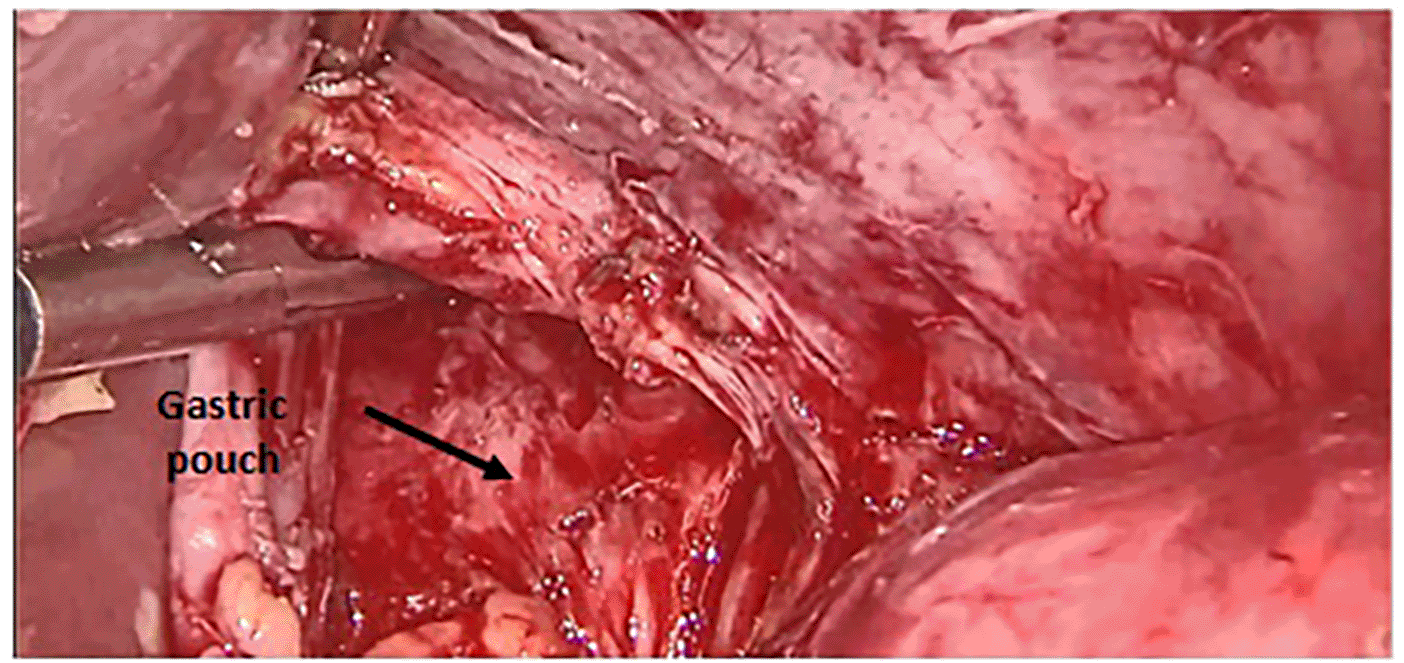

Surgery was then performed. After pneumoperitoneum was established using Hasson technique, dense adhesions between the gastric tube, the left hepatic lobe, and the left diaphragm were freed; using scissors to avoid energy related injuries. Peri-fistular fibrosclerosis made the dissection taut and hemorrhagic (Figure 1). There was a fistulous tract on the anterior aspect of the gastric pouch measuring 1 cm in diameter with hardened edges. To achieve tension-free fistula-jejunal anastomosis, the intra thoracic esophagus was freed (Figures 2 and 3). A jejunal loop, 60 cm from the ligament of Treitz, was raised and anastomosed manually in a termino-lateral fashion; with a running 4-0 vicryl thread (Figures 4 and 5). Surgical intervention was completed by drainage of the hiatal orifice. Our patient was discharged on the 10th POD and has remained well since then. Five years later, the patient did not report dysphagia or cough, and had a stable BMI.

3333b6e2-f1ad-4796-b1c5-60092c71668b_figure1.gif

Figure 1. Adhesiolysis of peri fistular fibrous adhesions.